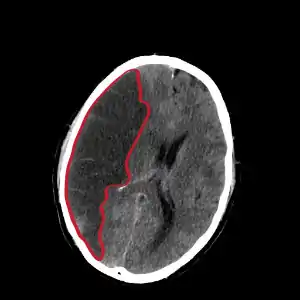

| CT scan slice of the brain showing a right-hemispheric cerebral infarct (left side of image). | |

Computed tomography (CT) and MRI scanning will show damaged area in the brain, showing that the symptoms were not caused by a tumor, subdural hematoma or other brain disorder. The blockage will also appear on the angiogram.